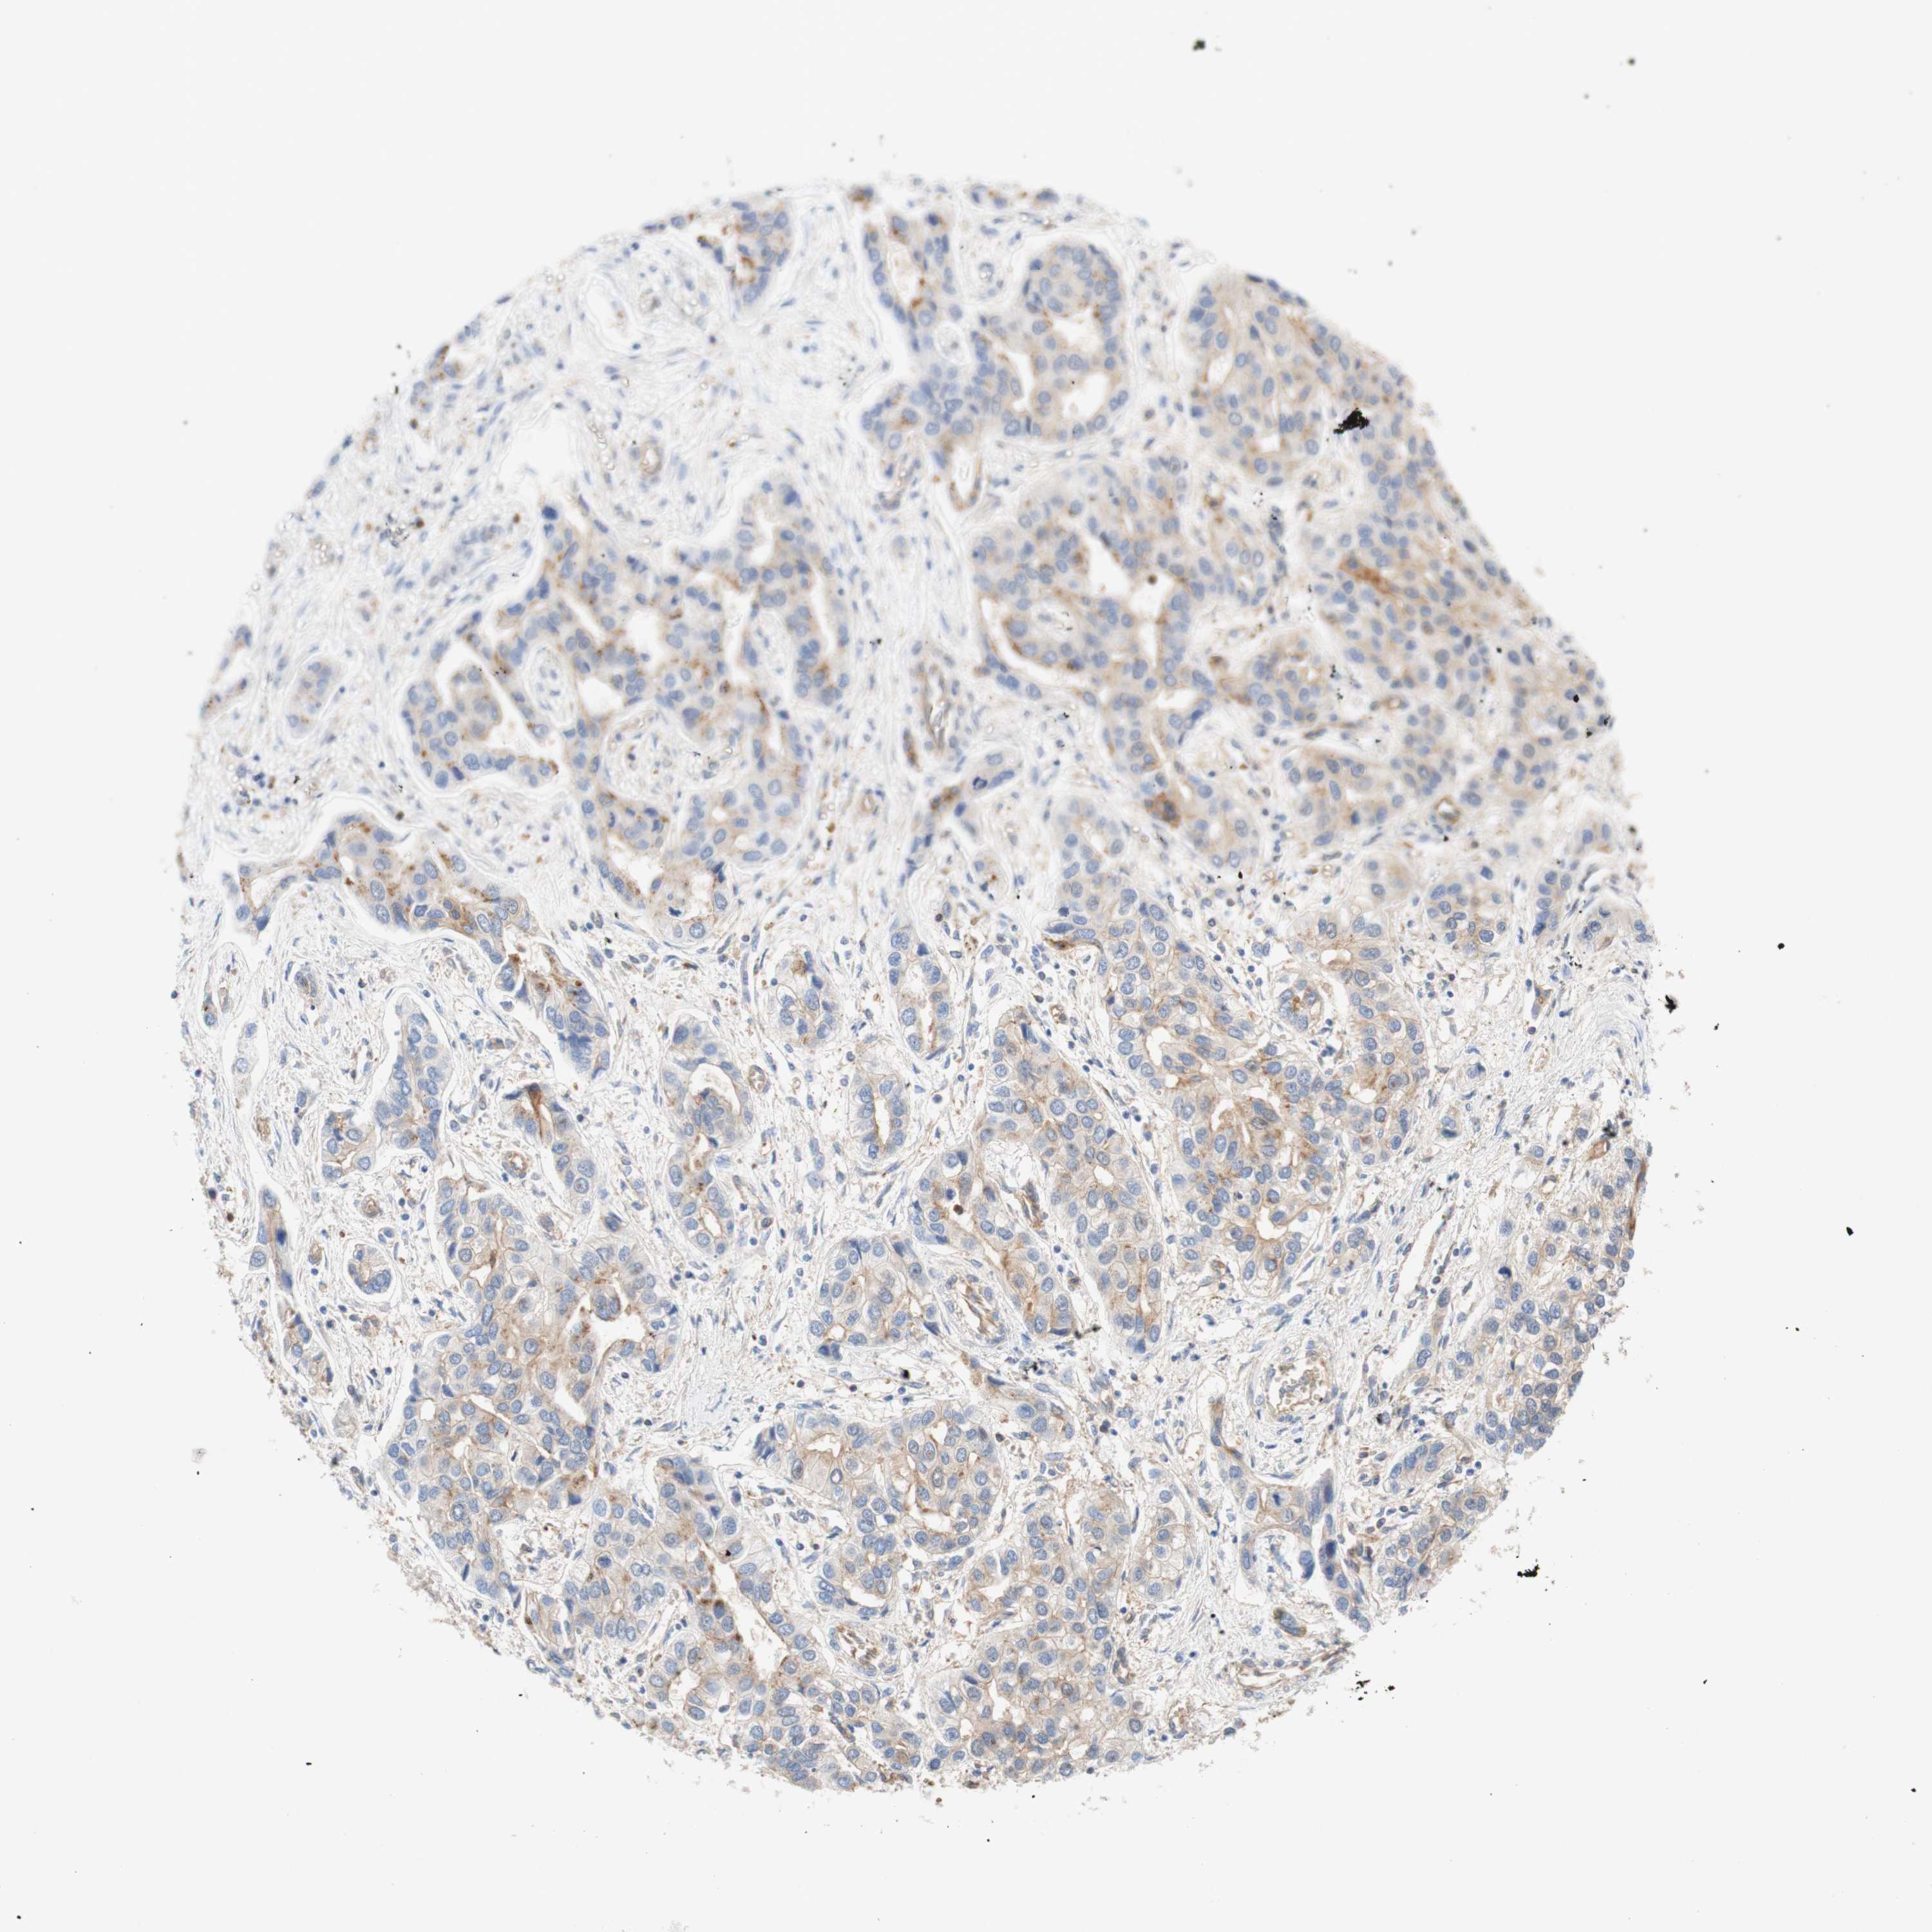

LIVER CANCER - Protein expressioni

A mouse-over function shows sample information and annotation data. Click on an image to view it in a full screen mode. Samples can be filtered based on level of antibody staining by selecting one or several of the following categories: high, medium, low and not detected. The assay and annotation is described here.

Note that samples used for immunohistochemistry by the Human Protein Atlas do not correspond to samples in the TCGA dataset.

Antibody stainingi

Antibody staining in the annotated cell types in the current human tissue is reported as not detected, low, medium, or high, based on conventional immunohistochemistry profiling in selected tissues. This score is based on the combination of the staining intensity and fraction of stained cells.

Each image is clickable and will lead to virtual microscopy that enables deeper exploration of all samples and also displays staining intensity scores, fraction scores and subcellular localization as well as patient and tissue information for each sample.

Antibody HPA010961

Antibody HPA011419

Staining

High

Medium

Low

Not detected

Intensity

Strong

Moderate

Weak

Negative

Quantity

>75%

75%-25%

<25%

None

Location

Nuclear

Cytoplasmic/membranous

Cytoplasmic/membranous,nuclear

Cholangiocarcinoma

Carcinoma, Hepatocellular, NOS